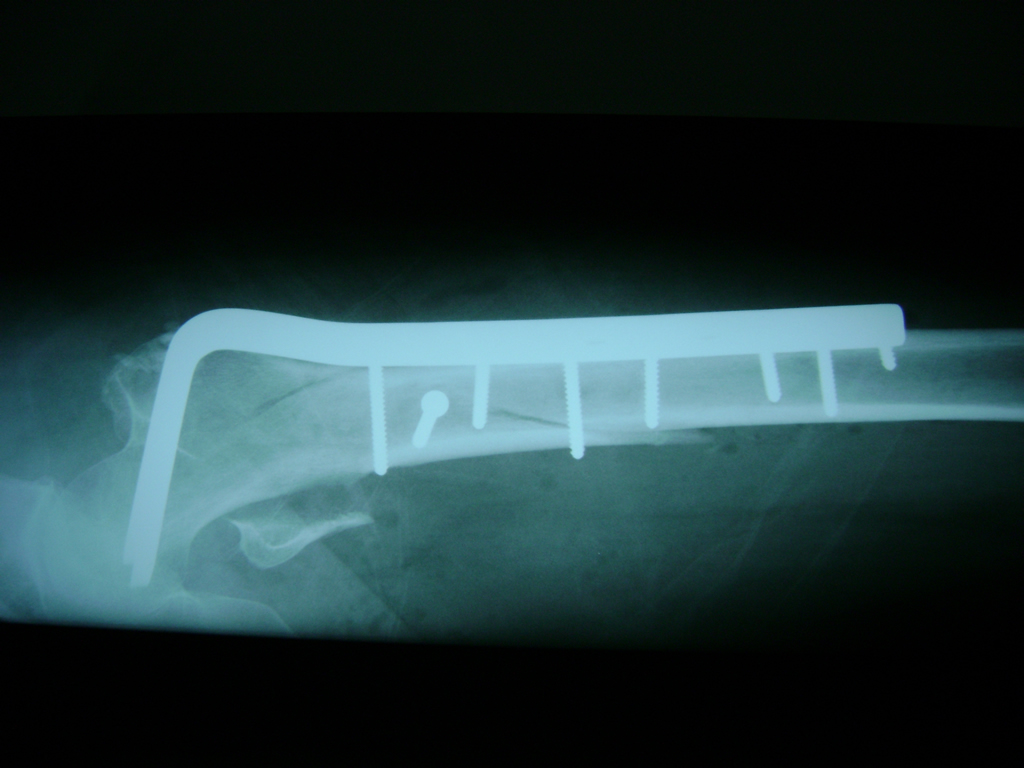

A menudo se recomienda la cirugía para reparar la fractura debido a dichos riesgos.

La cirugía de fractura de cadera se realiza para reparar una ruptura en la parte superior del hueso del muslo. Este hueso se denomina fémur.